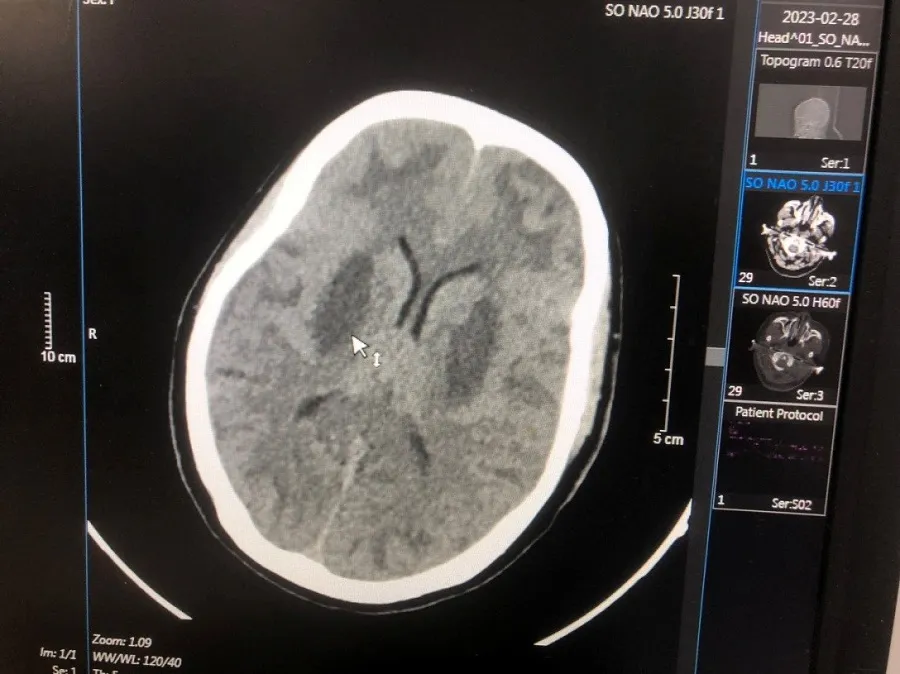

| Hình ảnh tổn thương não của BN TVN. Ảnh: BVCC |

Ca nặng thứ hai là TVN (17 tuổi, nam, dân tộc Dao, quê Cao Bằng) vào viện ngày 24-2. Bốn ngày trước khi vào viện, bệnh nhân thấy khó thở, mệt, mờ mắt, lơ mơ, hôn mê, ngừng thở.

Bệnh nhân được đưa đến Bệnh viện Đa khoa tỉnh Bắc Ninh cấp cứu. Sau đó được chuyển tới Trung tâm Chống độc Bạch Mai trong tình trạng hôn mê, tụt huyết áp, nhiễm toan chuyển hóa nặng, tổn thương não nặng hai bên, nồng độ methanol trong máu là 125 mg/dL, không có ethanol. Bệnh nhân được cấp cứu điều trị hồi sức giải độc lọc máu, hiện tri giác có cải thiện nhưng não vẫn tổn thương và phù não nhiều, tổn thương mắt.